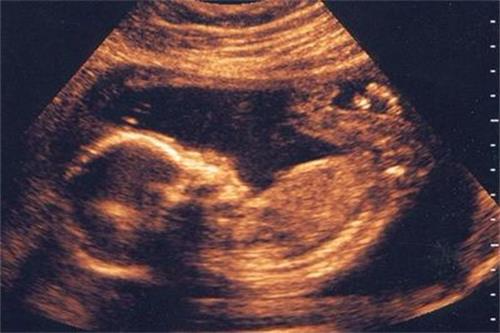

20周第三次产检

检查项目:四维彩超胎儿畸形筛查、复查血常规、尿常规、宫高、腹围、胎心、血压、体重

本次的四维彩超检查主要是看胎儿的头围、腹围、大腿骨长度等是否存在异常。